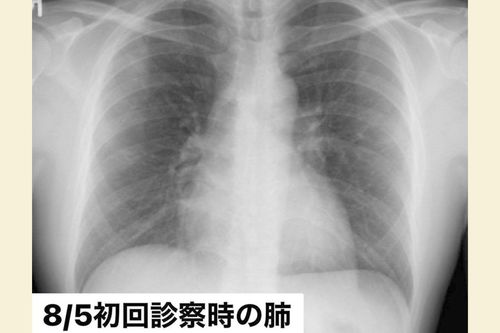

8月5日、「東京都発熱相談センター」で紹介された病院でのレントゲン写真。まだ肺はキレイだった(写真:取材者提供/東洋経済オンライン)

[写真 3/7枚目] 8月5日、「東京都発熱相談センター」で紹介された病院でのレントゲン写真。まだ肺はキレイだった(写真:取材者提供/東洋経済オンライン)